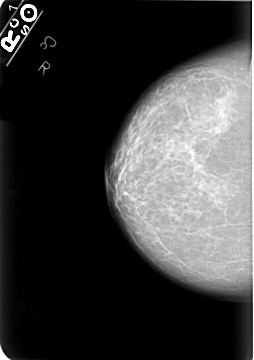

B_3017_1.RIGHT_MLO

RIGHT_CC LINES 5752 PIXELS_PER_LINE 4056 BITS_PER_PIXEL 12 RESOLUTION 50 NON_OVERLAY

RIGHT_MLO LINES 5776 PIXELS_PER_LINE 4080 BITS_PER_PIXEL 12 RESOLUTION 50 NON_OVERLAY